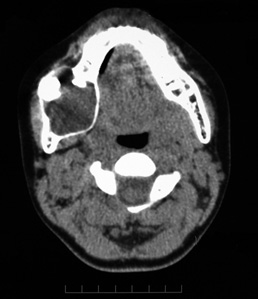

10歳 男児

X-pでは顎骨内に単房性の嚢胞様透過像を示すエナメル上皮腫の亜型。埋没歯をともなうことがあり画像のみでは含歯性嚢胞や他の嚢胞性病変との鑑別は難しい